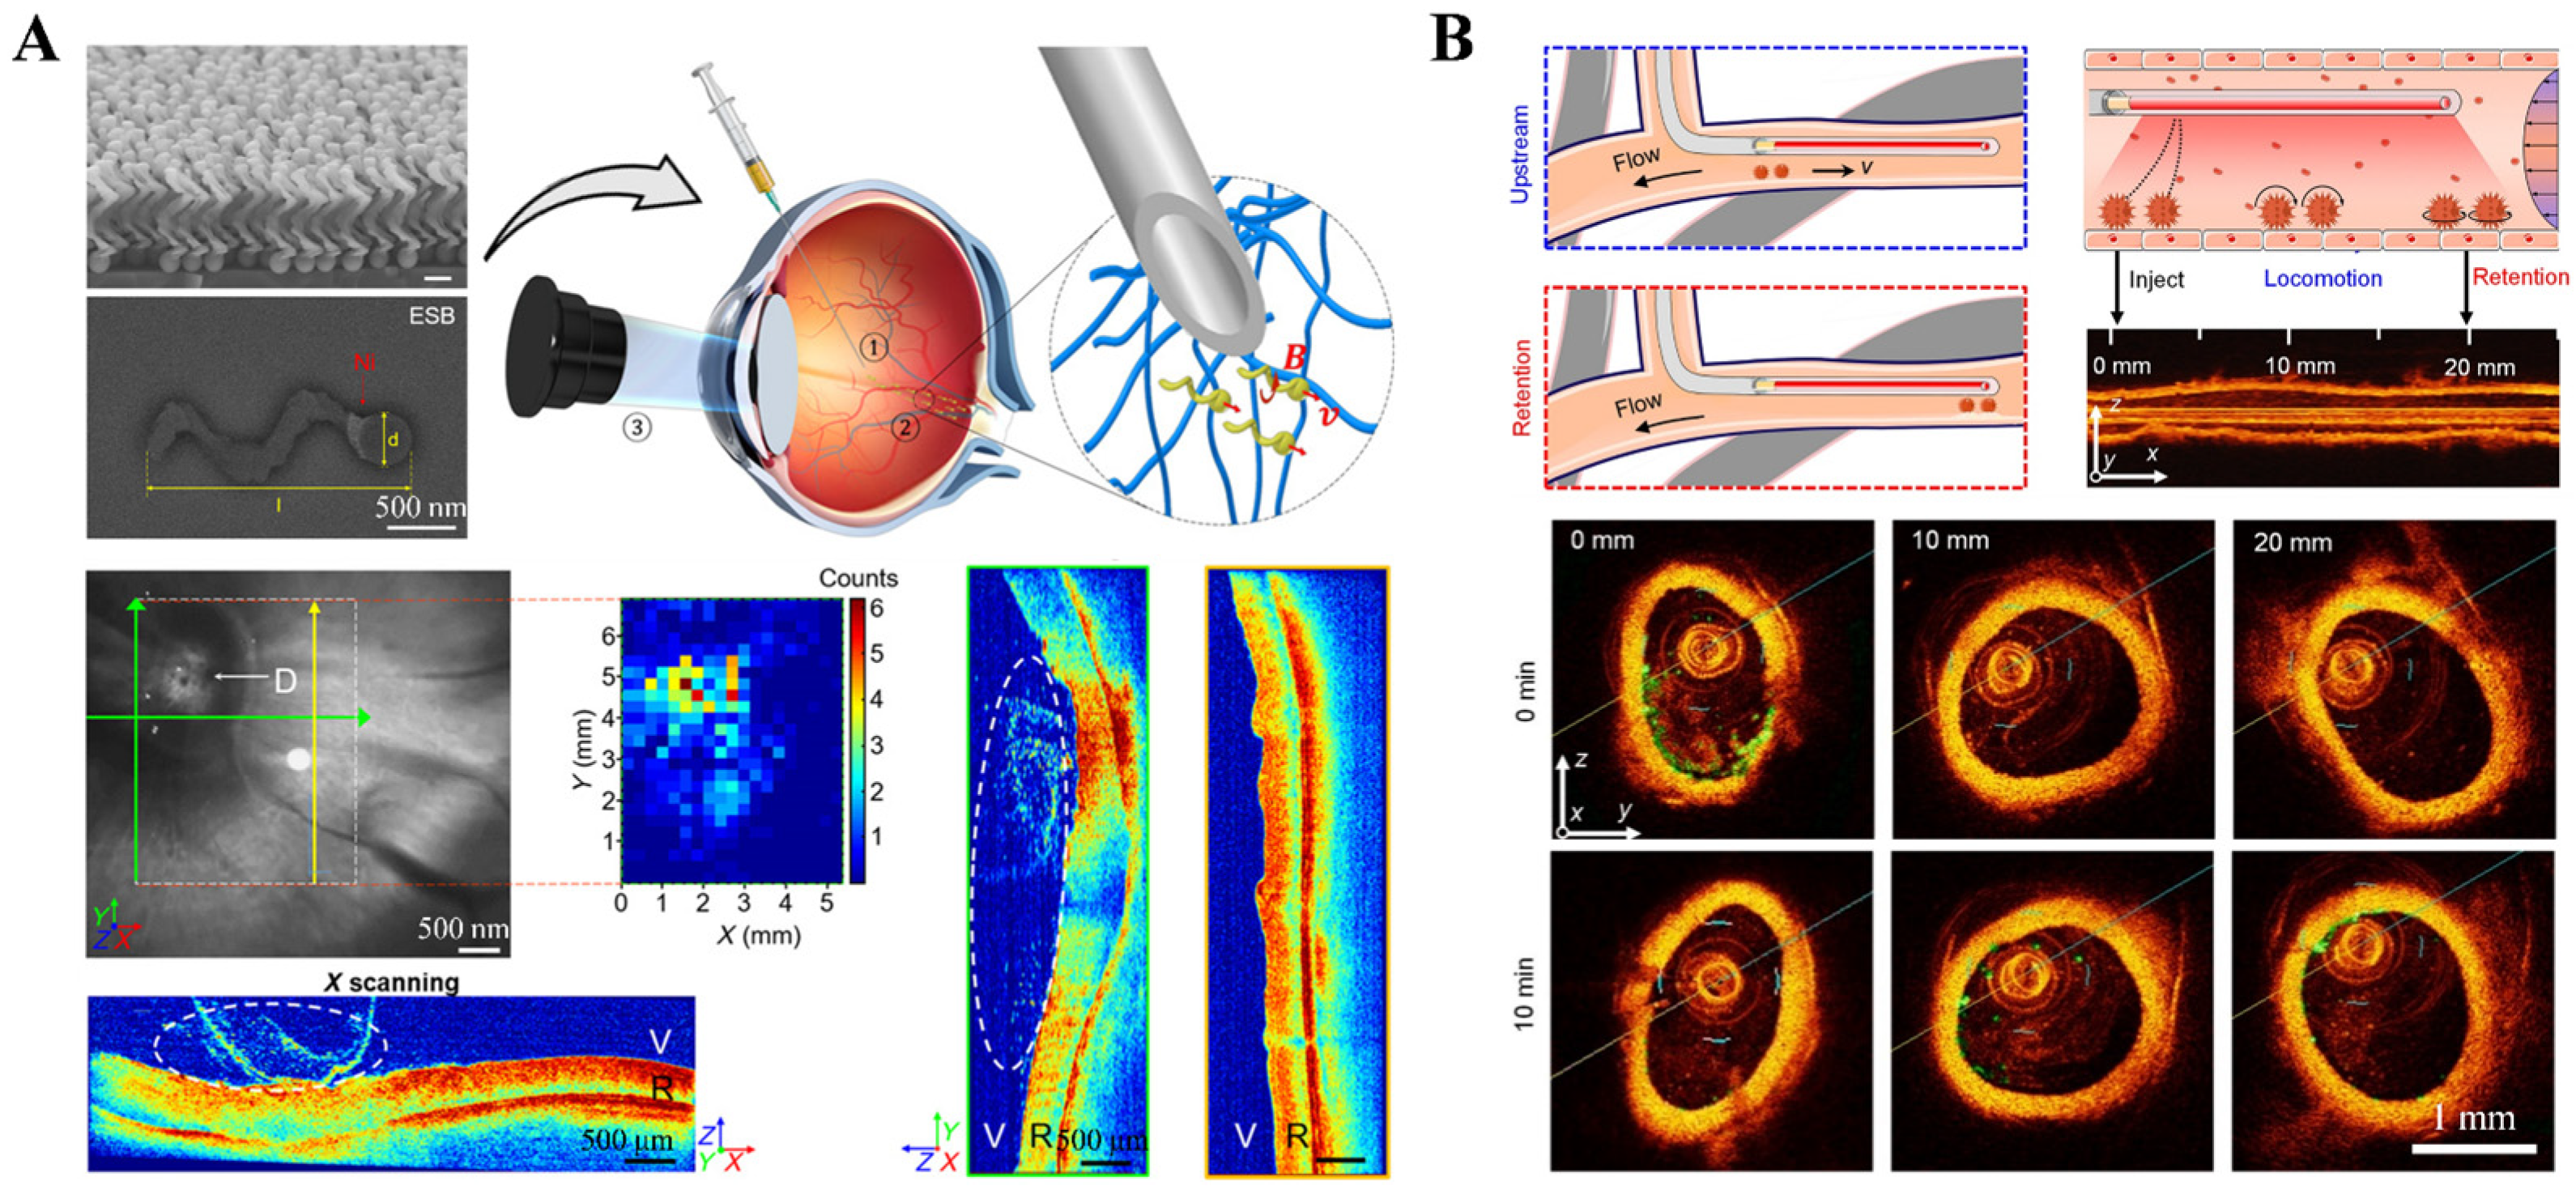

2.1.2. Optical Coherence Tomography (OCT) Imaging Technology

- Wu, Z.; Troll, J.; Jeong, H.-H.; Wei, Q.; Stang, M.; Ziemssen, F.; Wang, Z.; Dong, M.; Schnichels, S.; Qiu, T.; et al. A swarm of slippery micropropellers penetrates the vitreous body of the eye. Sci. Adv. 2018, 4, eaat4388. [Google Scholar] [CrossRef] [PubMed]

- Li, T.; Yu, S.; Sun, B.; Li, Y.; Wang, X.; Pan, Y.; Song, C.; Ren, Y.; Zhang, Z.; Grattan, K.T.V.; et al. Bioinspired claw-engaged and biolubricated swimming microrobots creating active retention in blood vessels. Sci. Adv. 2023, 9, eadg4501. [Google Scholar] [CrossRef] [PubMed]